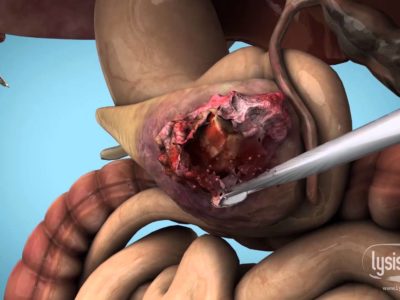

Pancreatic Cancer Animation

Pancreatic cancer 3D animation with microscopic view. Created by Lysis Media.